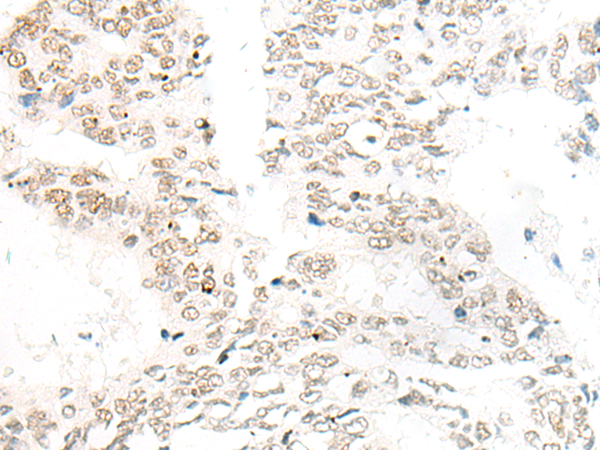

| IHCpositivecontrol: | HumancolorectalcancerandHumangastriccancer |

| IHCRecommenddilution: | 20-100 |